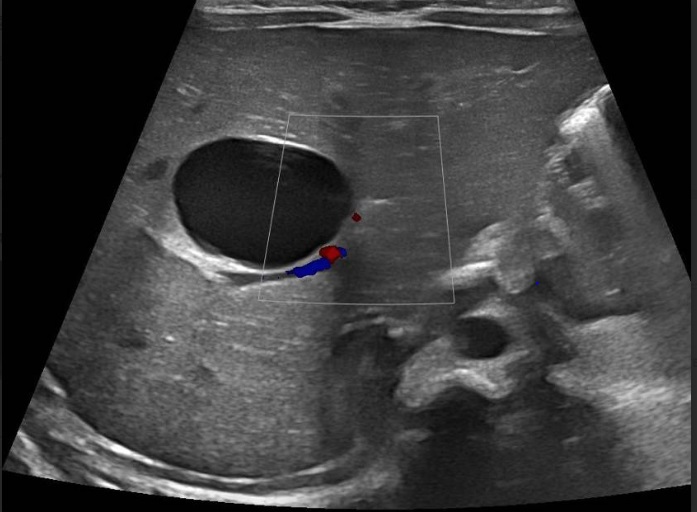

El parto tuvo lugar a las 38 semanas, eutócico y sin incidencias. A las 24 horas de vida, durante su estancia en Maternidad, se solicitó nueva ecografía abdominal, que mostró hallazgos compatibles con quiste simple hepático congénito, unilocular, de 2,5 cm, en segmento IV (Figura 2).

| Figura 2. Quiste hepático congénito. Quiste simple unilocular de pared fina en el interior del lóbulo hepático derecho, de 25 x 17 mm (ejes transverso y anteroposterior), en segmento IV. No se demuestra comunicación con la vesícula biliar ni con la vía biliar |